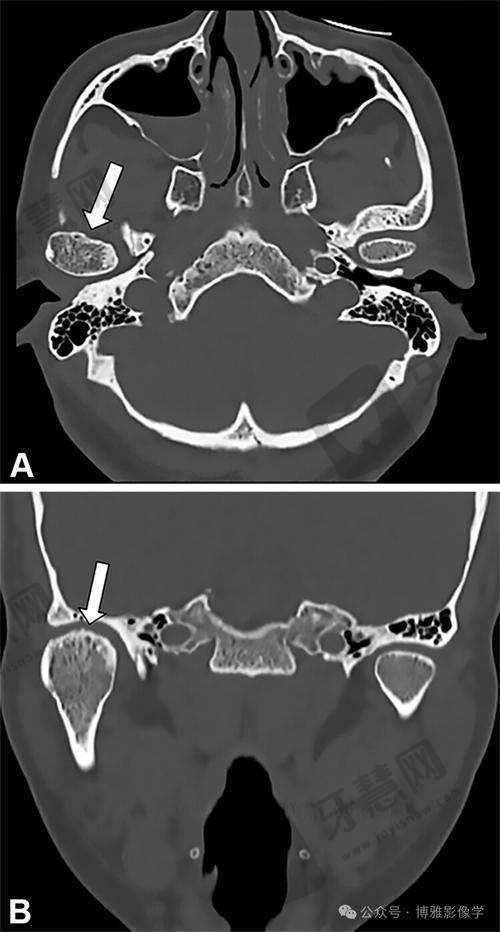

影像诊断:口腔CT三维重建技术,精细测量牙槽骨高度、密度,为种植、正畸提供科学依据。